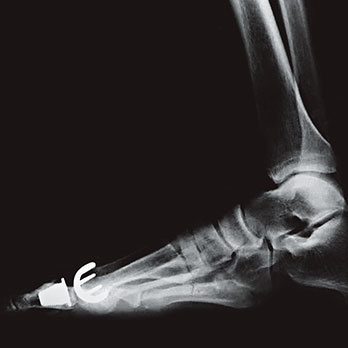

Abb. 2

Methode nach SCARF

Geringe Deformitäten mit wenig Beschwerden können mit Fussgymnastik, Schuhanpassungen oder häufig mit einer spreizfusskorrigierenden Schuheinlage, welche der Orthopädietechniker oder -schuhmacher anfertigt, korrigiert, respektive verbessert werden. Gröbere Verformungen bedürfen einer operativen Korrektur. Es gibt verschiedene Operationsverfahren. Ziel ist es, die Vorfussverbreiterung zu reduzieren und die Zehen wieder besser auszurichten. Die sanfteste operative Korrektur ist die Gelenks- oder Mittelfussköpfchen-Remodellierung. Hier wird das durch Verknöcherungen deformierte Köpfchen oder das gesamte Gelenk wieder in die ursprüngliche Form gebracht. Mit grösserem Aufwand werden Fehlstellungen durch Verschiebekorrekturen auf verschiedenen Höhen des Grosszehen-Mittelfussknochens sowie der Zehenglieder durchgeführt (Abb. 1). Diesbezüglich sind sehr viele verschiedene Operationsverfahren möglich. Ziel all dieser Korrekturen ist es, dass die ursprüngliche Fussform mit den physiologischen Auflageorten und der Kraftverteilung wieder hergestellt wird. Die aktuell meistgenutzte Korrekturoperation mit guten Möglichkeiten ist die Methode nach SCARF (Abb. 2), welche vom französischen Orthopäden Dr. Samuel Barouk entwickelt wurde. Sie beinhaltet eine seitliche, Z-förmige Mittelfussdurchtrennung mit Parallelverschiebung des vorderen Gelenksfragments zur 2. Zehe hin. Die Korrekturstellung wird anschliessend mit Spezialschrauben fixiert, und zur Entlastung des operierten Vorfusses wird ein Spezialschuh während 6 Wochen getragen.